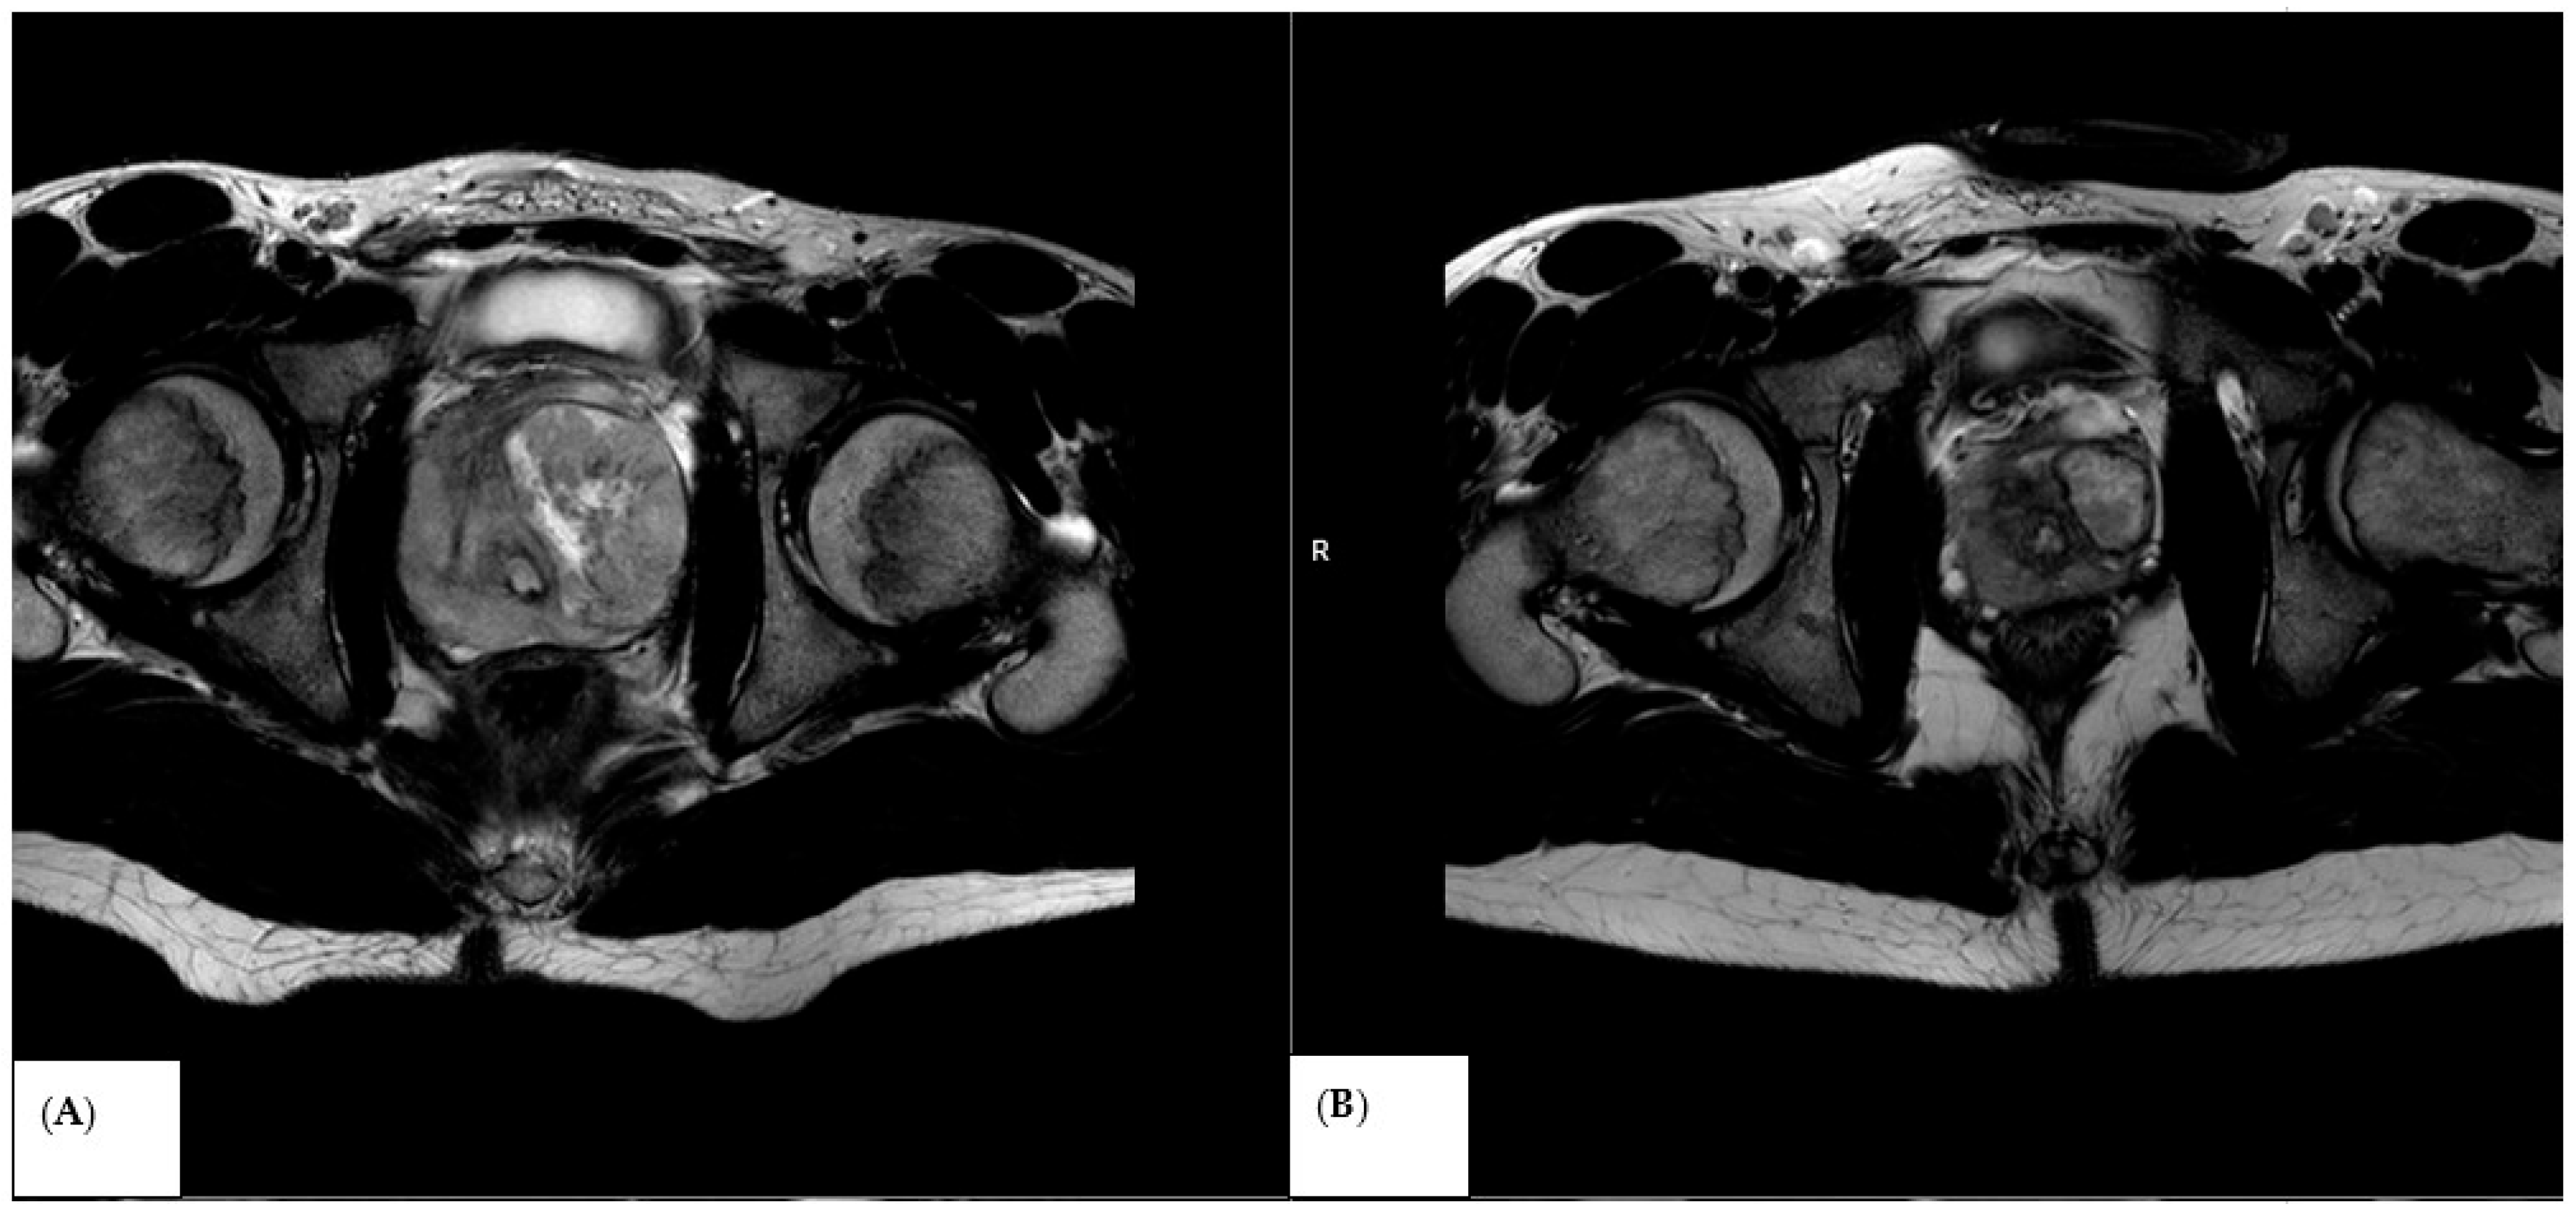

2.3. MRI Acquisition

2.4. Image Analysis and ADC Measurements

3.1. Baseline Diffusion Characteristics